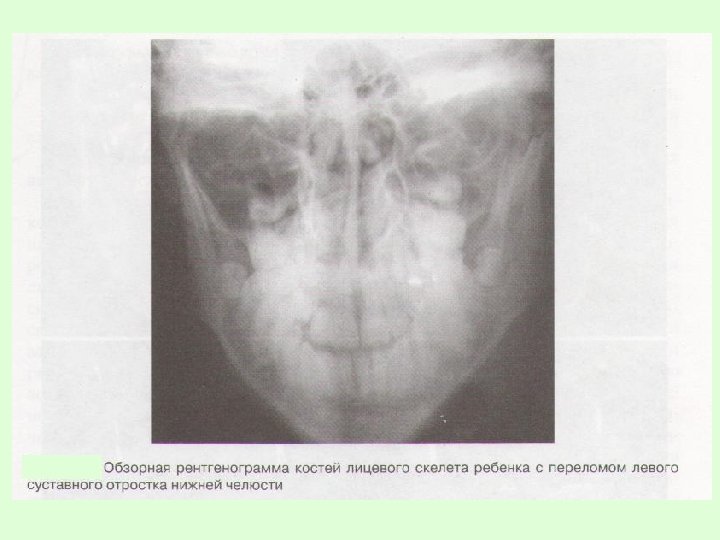

Заключительный диагноз перелома нижней челюсти ставят после проведения рентгенологического исследования в боковой укладке по Генишу или обзорной рентгенограммы нижней челюсти в прямой проекции, при переломе суставного отростка – ортопантомограммы или рентгенограммы сустава по Шуллеру или Парма.

На рентгенограммах обычно определяется нарушение целостности костной ткани, наличие линии перелома, смещение отломков челюсти. В сложных диагностических случаях переломов суставного отростка нижней челюсти у детей для постановки окончательного диагноза при отсутствии явных клинических и рентгенологических признаков используют метод спиральной компьютерной томографии с мультипланарной реконструкцией.